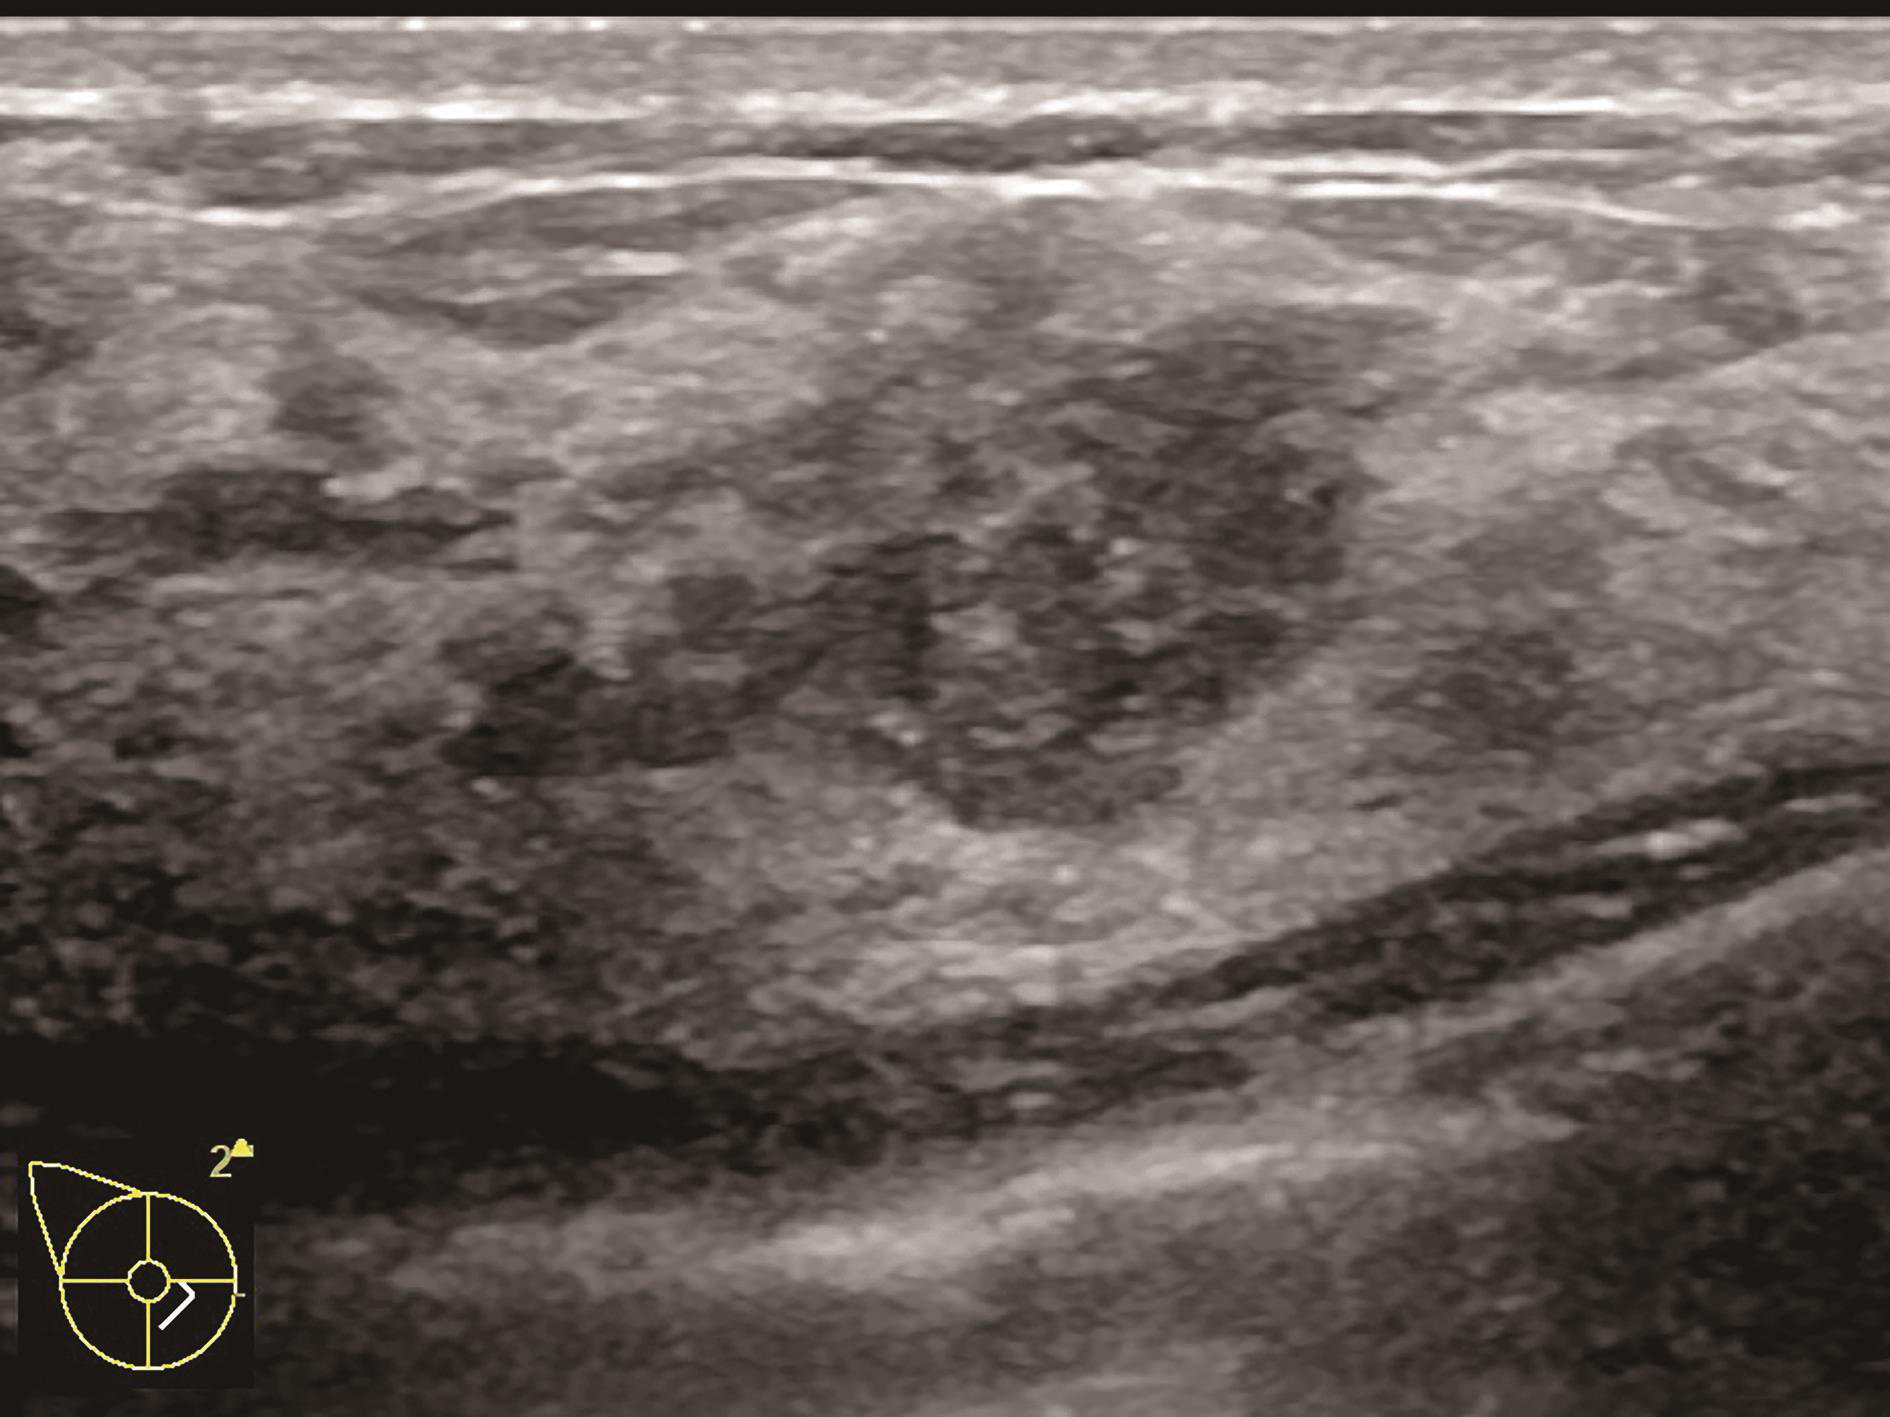

造影前应用传统灰阶超声全面扫查患侧乳腺及腋窝,重点扫查既往检查可疑病灶所在象限,结合既往检查确定超声造影靶目标及造影切面。评估病灶所在部位乳腺腺体致密性,二维及彩色多普勒(CDFI)超声常规检测肿块的大小、形态、边界、内部回声、血流及与周边组织的关系,充分利用现有超声新技术(如弹性成像)全面评估病灶。当病灶位置表浅、位于乳头后方或与探头耦合不佳时,可应用超声垫。

图2-2-1 确定造影病灶

A.病灶二维图像;B、C.病灶CDFI图像;D.同侧腋窝淋巴结情况;E.病灶弹性成像图像